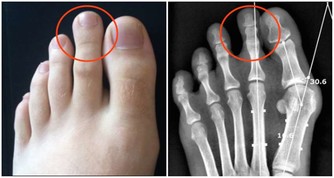

鞋底內側的磨損較多,俗稱內八字,腳板過度內翻或是先天性的扁平足,膝關節向內側壓縮,易導致關節扭傷、損傷。

5、鞋底外側的磨損較多

鞋底外側的磨損較多,俗稱外八字,腳板過度外翻或是先天性的高弓足,膝關節向外側壓縮,嚴重時形成O型腿。

B.鞋跟內側都出現磨損

這種情況,是因為兩腿的膝關節向外分離、小腿脛骨向內翻轉了一定角度造成的。如果磨損十分嚴重,就意味著你的膝蓋已經外移,雙腿已經變形,變成「O形腿」或「內八字」。

隨著年齡增長,這種情況容易導致膝關節疼痛以及加速關節退化,甚至引起腰椎不適。